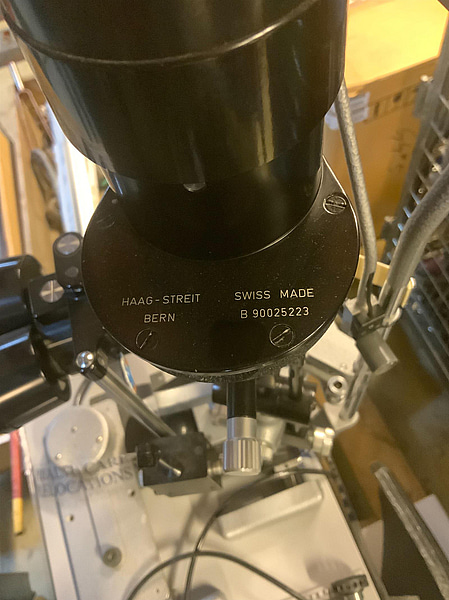

Not allowedSpaltlampa Haag Streit 900

B90025223

M90025223

Se bifogad dokumentation.Beskrivning på engelska, res. för felskrivning: